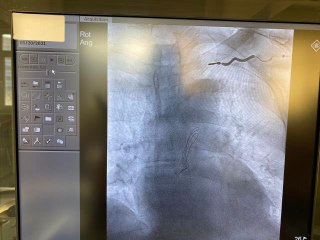

Sivas'ta bir yolcu otobüsünde kalp pili duran genç kızı şoför hastaneye yetiştirdi.